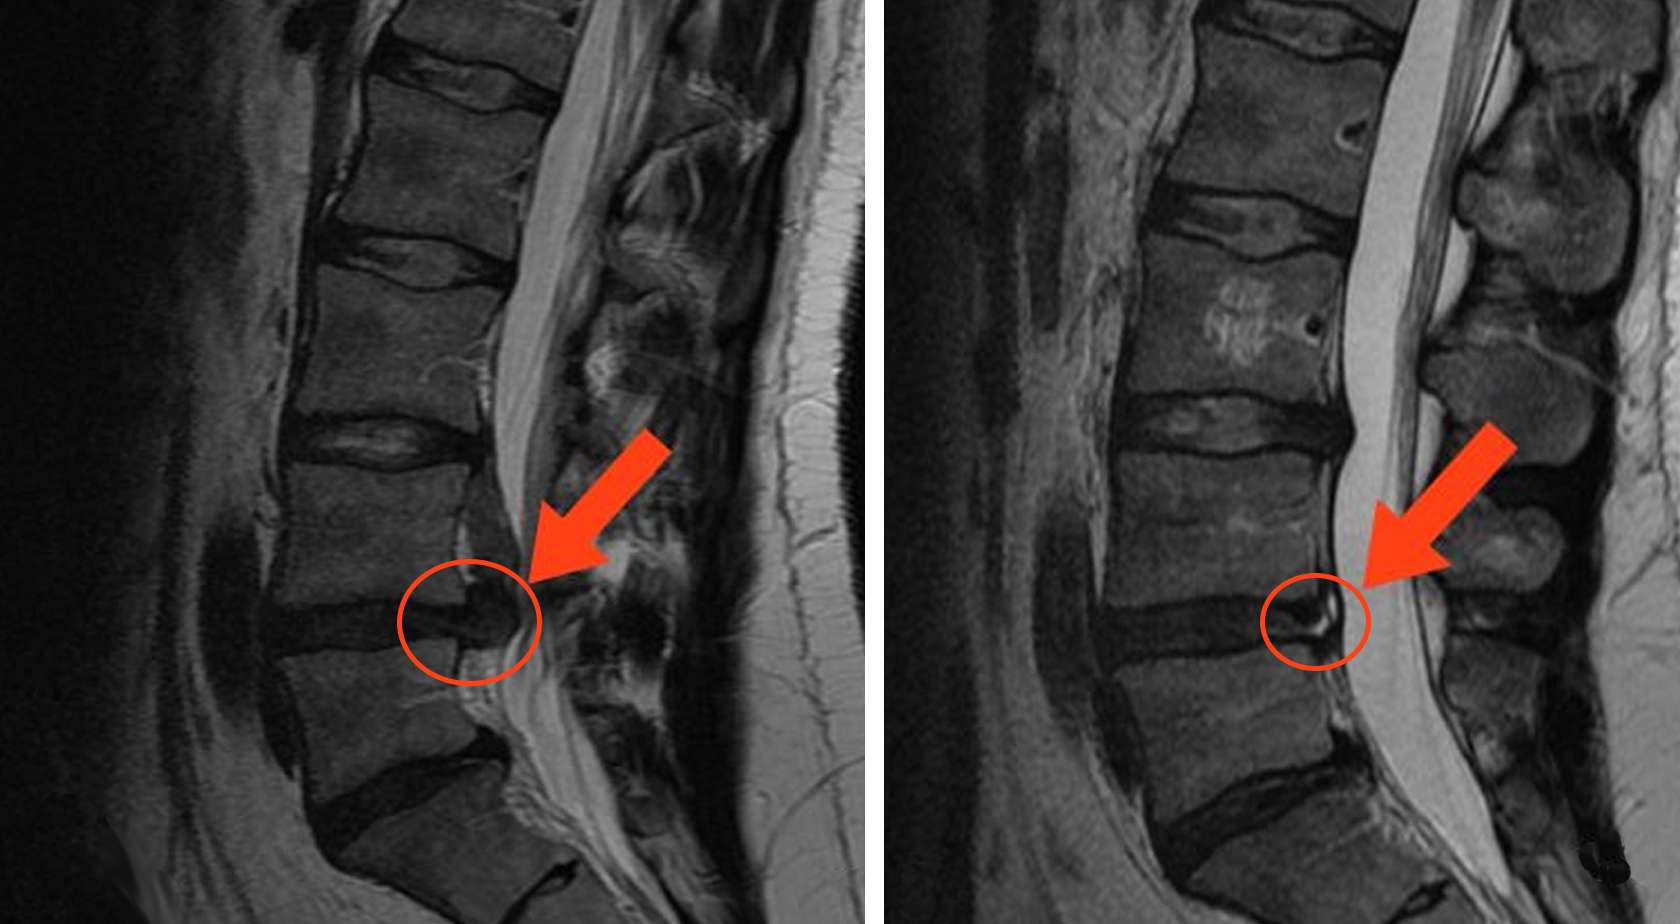

Резорбция межпозвонковой грыжи

Резорбция межпозвонковой грыжи – это комплекс мероприятий, направленных на уменьшение объема образования вплоть до полного его рассасывания. Процедуры стимулируют работу иммунных клеток организма, разрушение патологически измененных тканей и их реорганизацию с последующим рубцеванием. Комплексное воздействие способствует ускорению этих процессов.

Иммунитет воспринимает компоненты грыжи как чужеродный объект и запускает активные воспалительные процессы. Структуры постепенно пронизываются кровеносными сосудами, что позволяет иммунным клеткам работать более активно. Постепенно клетки грыжи разрушаются, ткани реорганизуются, поврежденное фиброзное кольцо замещается рубцовой тканью. Патологическое образование исчезает или значительно уменьшается в размерах. Если грамотно влиять на эти процессы, подстегивая, а не тормозя их, можно добиться впечатляющих результатов без применения хирургических технологий.

Результаты до и после